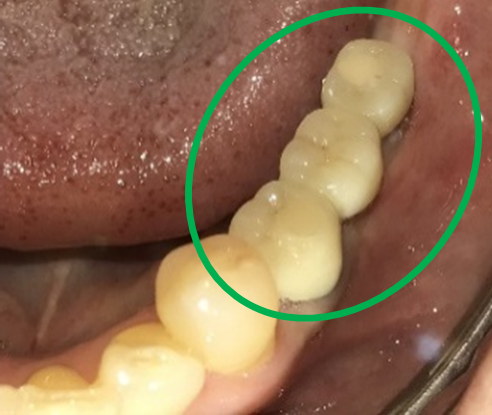

After

※緑丸は、今回埋入したインプラント

※黄色丸は、2006年10月に埋入したインプラント